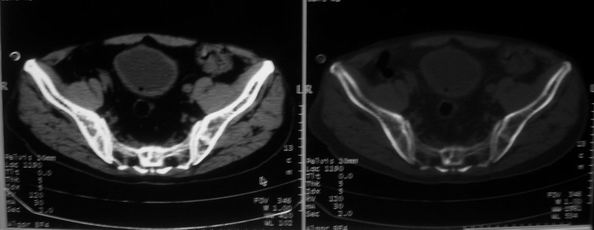

男,85岁,排尿困难。骶椎有问题吗?

1)考虑前列腺增生症并阻塞性膀胱炎。2)骶椎右侧类似囊状骨质密度减低区,边缘骨质硬化,其内为软组织密度影填塞,相邻之骶椎椎管受压变形;考虑为骶椎右侧囊肿或神经纤维瘤。

建议:行mri检查。

1)前列腺明显增大,突入膀胱,各叶比例协调,密度均匀,精囊腺及精囊角正常;考虑前列腺增生症并阻塞性膀胱炎。2)骶椎右侧类似囊状骨质密度减低区,边缘骨质硬化,其内为软组织密度影填塞,相邻之骶椎椎管受压变形;考虑为骶椎右侧囊肿或神经纤维瘤。